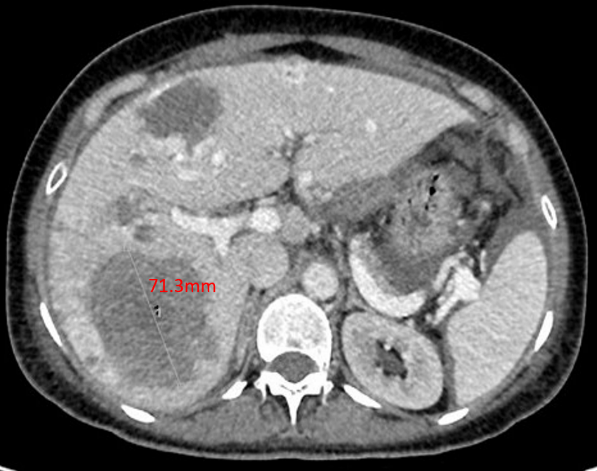

绒患者,张某,女,51岁。主诉:停经伴左中下腹痛4+月 现病史:患者既往月经规律,周期30天,LMP 2021年7月14日。停经后无恶心、呕吐等不适。G3P2A1,足月顺产两次,末次妊娠为7年前,行人工流产终止妊娠,此后以避孕套避孕。4月余前无明显诱因出现左中下腹隐痛,休息后可缓解,无进行性加重,无排便习惯改变等。2021年10月30日就诊于当地医院,彩超示:肝内多发高回声结节,血管瘤?其他不排。左侧腹腔内低回声包块,性质待定,腹腔少量积液。CT提示:左侧腹部占位性病变,考虑来源于腹腔,性质待查,纤维瘤?间质瘤?其他?转诊至当地上级医院,行电子直-结肠镜示:乙状结肠病变性质待查。CT示:1.左侧腹腔内肿块灶:间质瘤?炎性肌纤维母细胞瘤?2.肝内多发结节灶:转移瘤;3.子宫肌层内结节灶:子宫肌瘤?4.右侧附件区不规则肿块:粘液囊腺瘤可能性大;5.宫颈左后上方结节灶:转移瘤?6.盆腔少量积液;7.腹腔内多发小淋巴结。在超声引导下行左上腹腹腔肿块穿刺活检,穿刺组织3条,全部为凝固性坏死组织,倾向恶性肿瘤。2021年11月1日血清hCG 830 mIU/ml。2021年11月8日再次转诊至广州某医院,行肝部肿物穿刺,病理示:(肝肿物)结合免疫组化[β-HCG(+),GATA-3(+),p63(部分+)]考虑为绒毛膜上皮癌可能性大。2021年11月17日血清hCG >100万 mIU/ml。为进一步诊治,请我院进行院际会诊后,予以EP方案化疗1程后转入我科。 月经婚育史:12岁初潮,周期30天,经期5天,LMP 2021年7月14日,量中,无痛经。生育史同前。 个人史和家族史:无特殊。 体格检查:T 36.3℃,P 102次/分,R 20次/分,BP 120/80mmHg,身高156cm,体重50kg。左侧中下腹部触诊可及一约15cm×10cm边界不规则的质硬肿物,活动度差,轻压痛。 妇科检查:外阴未见异常;阴道通畅,各壁未见紫蓝色结节;宫颈正常大小,光滑,无接触性出血;宫体前位,大小基本正常,活动度差;双侧附件区未及异常肿物;三合诊:道格拉斯窝处可及一边界欠清肿物,触痛不明显,双侧宫旁无增厚,指套退出直肠无血染。 辅助检查: 全腹部CT平扫+增强+三维重建:腹腔大量积液,脂肪间隙模糊并多发渗出;肝内多发转移瘤并部分瘤内出血;左中腹肝胃间隙、脾胃间隙及子宫直肠间隙肿块,考虑转移瘤。 胸部CT:双肺散在实性结节,考虑转移瘤。 头颅MR平扫+增强:未见异常。